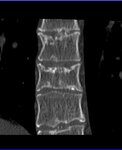

Ein Foto meiner "inneren Schönheit" hab ich mal angehängt.

Ein Foto meiner "inneren Schönheit" hab ich mal angehängt.